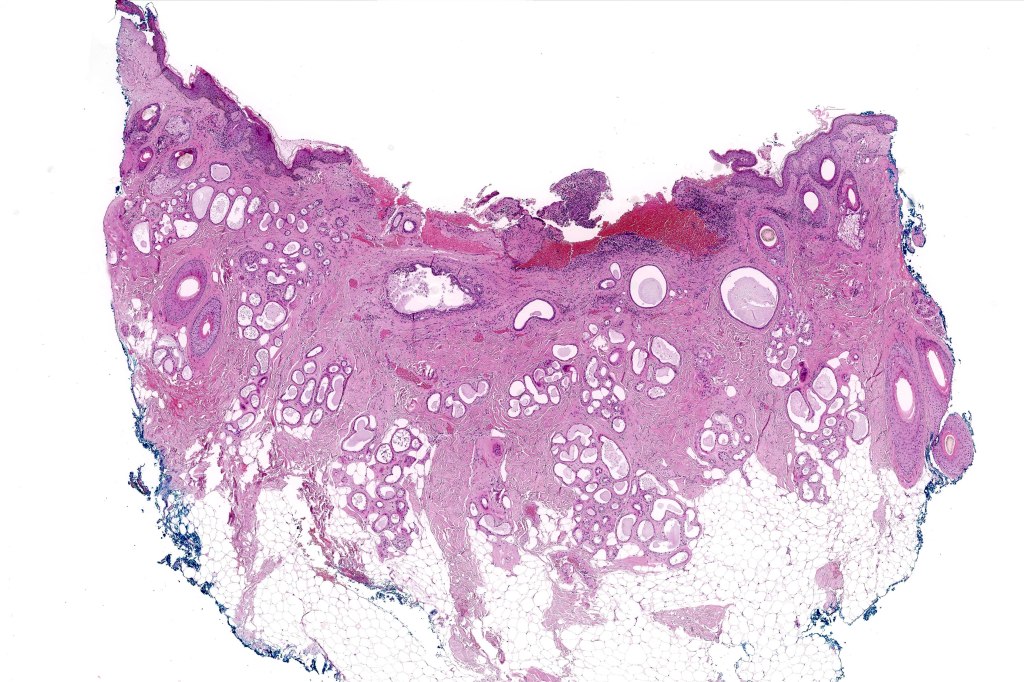

Histological features

•May develop in a background of a benign precursor tumor or exceptionally nevus sebaceus

•Poorly circumscribed tumor nodule with invasive border

•Rarely cystic

•Variable glandular, tubular, papillary, tubulo-papillary, diffuse and solid growth patterns